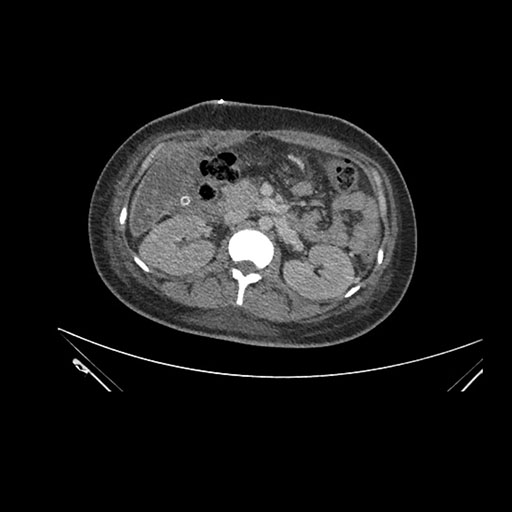

Axial Arterial